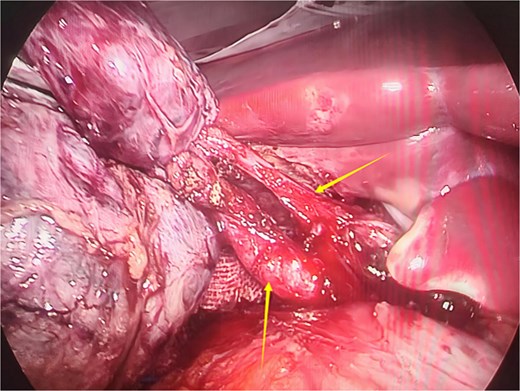

Given the patient’s recurrent biliary colic, laparoscopic cholecystectomy was decided. During surgery, adhesions between the gallbladder and the surrounding omentum were carefully dissected. After mobilizing the hepatic porta, the anatomy of Calot’s triangle was meticulously identified, confirming the double gallbladder malformation as preoperatively suspected. The two gallbladders had independent cystic ducts draining into the common hepatic duct (Fig. 3). The lateral gallbladder contained multiple stones, while the medial one was stone-free. A single cystic artery, originating from the right hepatic artery, was observed passing posteriorly between the two cystic ducts before supplying the gallbladders. The cystic ducts were sequentially clipped and transected using bioabsorbable clips. Postoperative specimen dissection revealed two gallbladders measuring 8.5 × 3.0 cm and 8.5 × 2.5 cm, respectively. The serosal surfaces of the two gallbladder bodies were adherent, and each had an independent cystic duct inserting into the common hepatic duct, confirming an "H-type" double gallbladder malformation (Fig. 4). Pathological examination reported a double gallbladder malformation: one with a slightly roughened mucosa, wall thickness of 0.2 cm, multiple stones, and features of adenomatous cholecystitis; the other with a smooth mucosa, wall thickness of 0.1 cm, and no significant stones. The patient recovered well and was discharged on the first postoperative day.

Intraoperative image showing two cystic ducts, each indicated by an arrow.